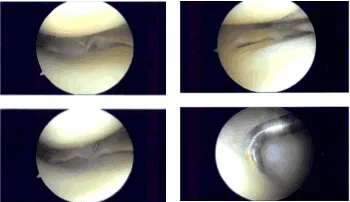

Medial anterior portal was made with the use of a spinal needle and knife. Examination of the medial femoral compartment showed horizontal and oblique tear of the lateral free margin along the body of the posterior hom. This was done with the use of straight biters and shavers.

Balanced margins could be achieved. Examination of the rest of the tibiofemoral compartment was good. Examination of the infrapatellar notch showed an intact ACL. Examination of the lateral tibial compartment showed intact meniscus.

There was Grade III medial injury to the articular cartilage which was debrided to balanced margins. The bone was then exposed. Examination of the patellofemoral compartment showed intact cartilage. Final pictures were taken and saved.

Intraoperative Arthroscopy Images